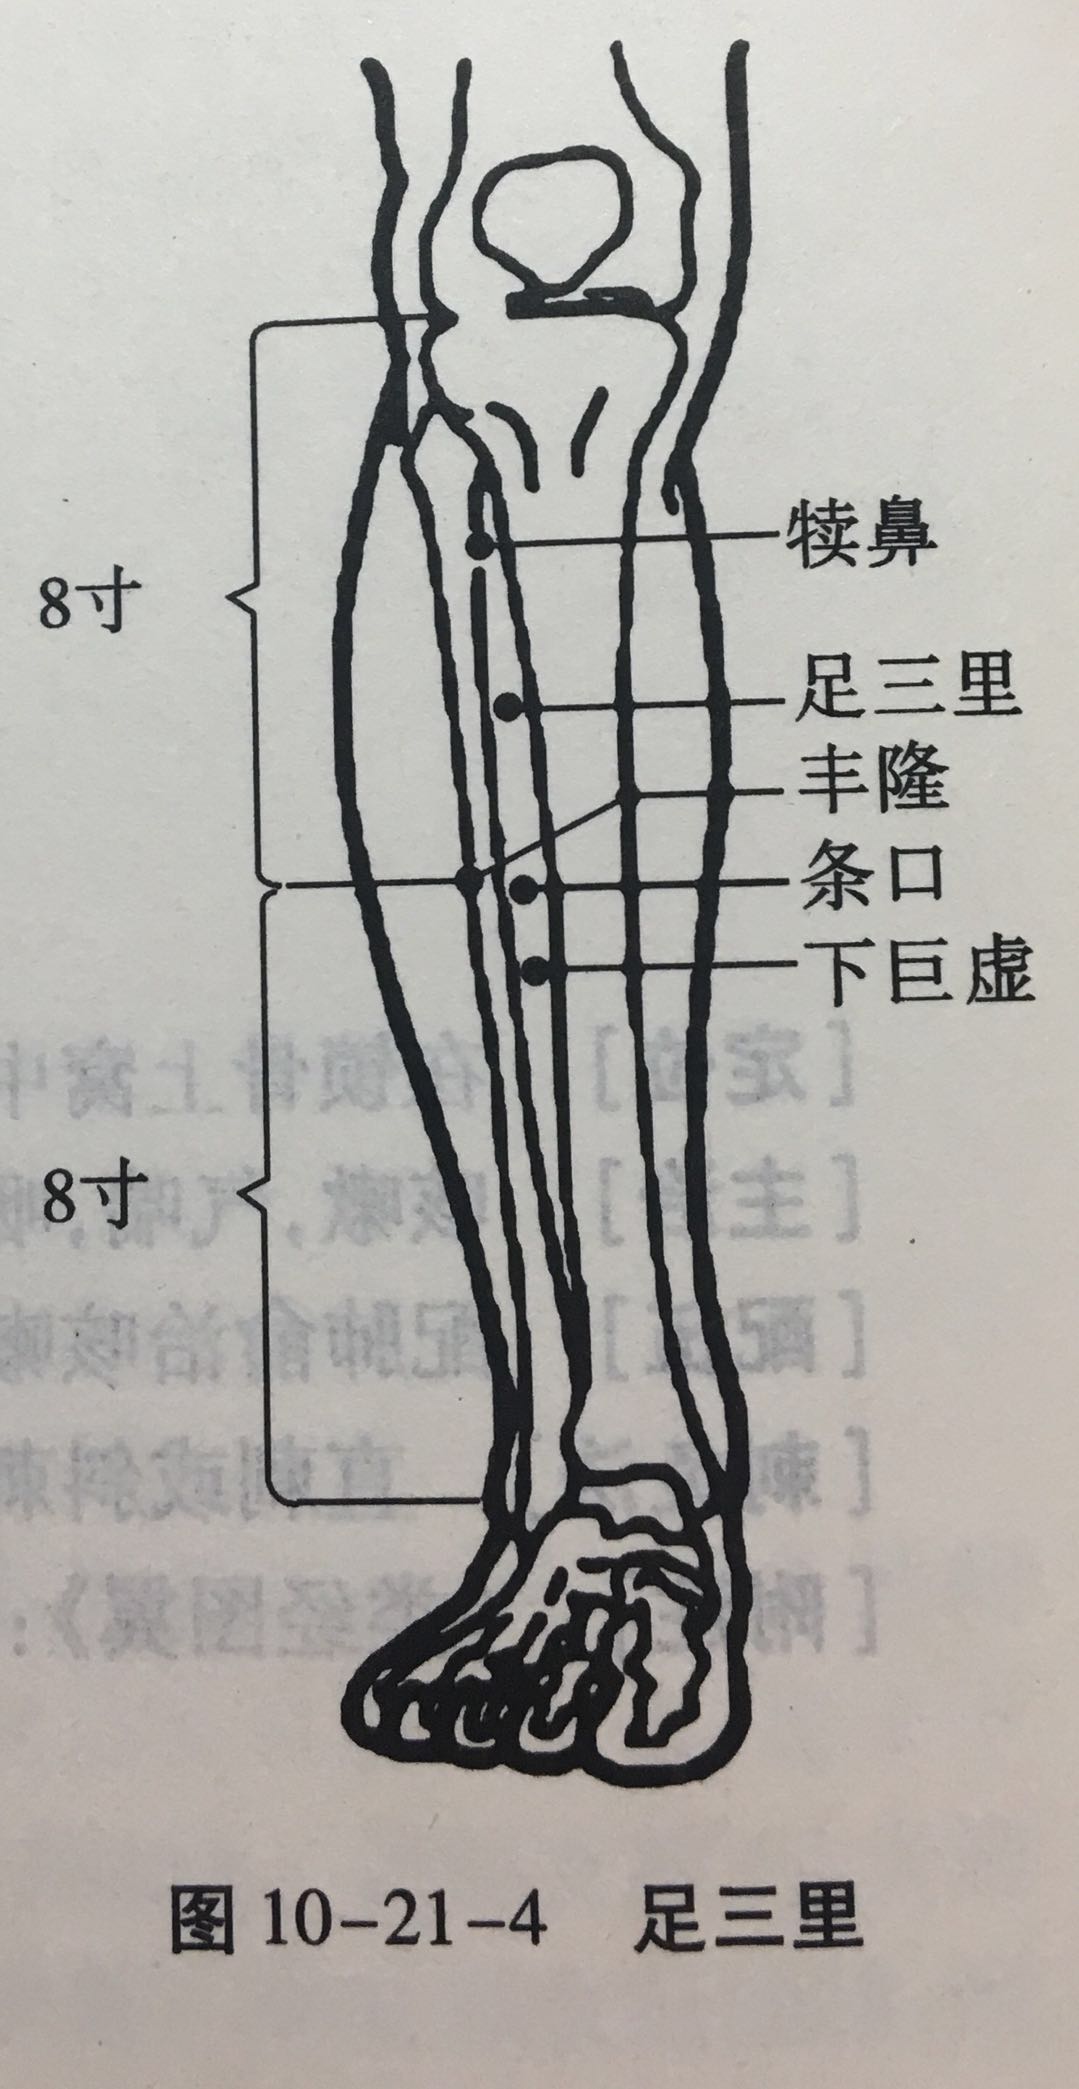

足三里

【定位】 在小腿前外侧,当犊(dú)鼻下 3 寸,距胫骨前嵴(jí)外 1 横指(中指)(图 10-21-4)。

【主治】 胃痛,呕吐,噎(yē)膈,腹胀,泄泻,痢疾,便秘,乳痈,肠痈,下肢痹痛,水肿,癫狂,脚气,虚劳羸(léi)瘦。

【配伍】 配中脘、梁丘治胃痛,配内关治呕吐,配气海治腹胀,配膻中、乳根治乳痈,配阳陵泉、悬钟治下肢痹痛,常灸足三里可养生保健。

【刺灸法】 直刺 1 ~ 2 寸,强身健体用灸法。

【附注】 (1)足阳明经所入为“合”;胃的下合穴。(2)本穴有强壮作用,为保健要穴。(3)参考资料:①据报道,针刺健康人和胃病患者的足三里和手三里,观察发现胃驰缓时针刺收缩加强,胃紧张时变为弛缓,并可解除幽门痉挛。②据报道,针刺单纯性消化不良和中毒性消化不良患儿的足三里、合谷、三阴交,可使原来低下的胃游离酸、总酸度、胃蛋白酶和胃脂肪酶活性迅速升高。③据报道,针刺人及家兔的足三里,发现裂解素(主要是裂解素含有大量多糖体的革兰氏阴性杆菌,也能灭活某些病毒)都有增加,人增加 17.85 单位,兔增加 62.1 单位,两者均在针后 12 小时增加最明显。④据报道,针刺家兔的“足三里”“大椎”可使其调理素明显增加,从而促进白细胞吞噬指数的上升,增强其免疫能力。

丰隆

【定位】 在小腿前外侧,当外踝尖上 8 寸,条口外 1 寸,距胫骨前嵴外 2 横指(中指)(图 10-21-4)。

【主治】 头痛,眩晕,痰多咳嗽,呕吐,便秘,水肿,癫狂,痫症,下肢痿痹。

【配伍】 配风池治眩晕,配膻中、肺俞治痰多咳嗽。

【刺灸法】 直刺 1 ~ 1.5 寸。

【附注】 足阳明经络穴。